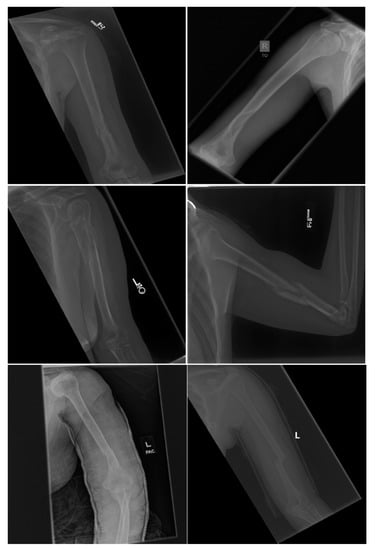

Both DenseNet-201 and InceptionResNetV2 models show a high sensitivity greater than 0.9. Figure 6 shows examples of the humerus that were classified correctly as abnormalities by DenseNet-201 model, whereas DenseNet-169 could not classify these as abnormalities. There were 17 such images in the test set that DenseNet-201 was able to classify correctly but DenseNet-169 could not. There was only one abnormal image where DenseNet-169 did better in recall compared to DenseNet-201. With the availability of larger training datasets, the ability of the more complex DenseNet-201 and InceptionResNetV2 to exploit additional feature information in the data as compared to DenseNet-169 may allow for further increase in relative accuracies of these models to demonstrate a performance difference at 95% CIs.

Figure 6.

Examples of Humerus abnormalities correctly classified by DenseNet-201 and incorrectly classified by DenseNet-169.